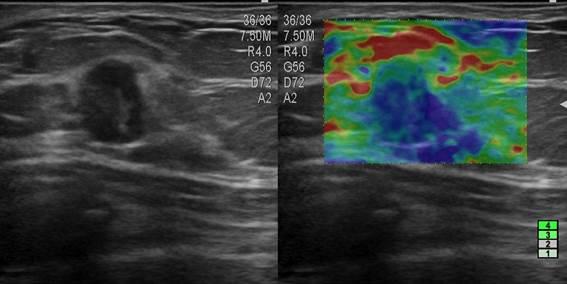

Ung thư tuyến vú

» Thông tin: Nữ giới – 45 tuổi.

» Lâm sàng: Kiểm tra sức khỏe.